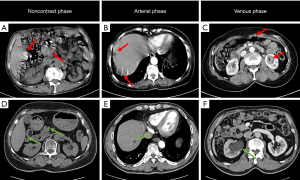

Group 1 demonstrated significantly fewer motion artifacts in the lung (P=0.027) and mediastinum (P<0.001) than did Group 2 (Table 2 and Figure 2). Although no statistical difference was observed in overall image scores, they were consistently higher in abdomen in Group 1 than in Group 2 (Figure 3). Comparable results were found for pelvic image quality, image noise, organ enhancement, and lesion conspicuity (P>0.05; Figure 4). The percentage of images with significant motion artifacts in mediastinum was significantly lower in Group 1 than in Group 2 (Reader 1: 1.2% vs. 30.6%; Reader 2: 2.4% vs. 32.9%; P<0.001; Table 3). No statistically significant differences were observed in the severity distribution of artifacts between the lung, abdomen, and pelvis in Group 1. The intraobserver (κ=0.788–0.964) and interobserver agreement (κ=0.708–0.929) in the subjective image quality analysis was good to excellent.

In the field of abdominal and pelvic imaging, several studies have evaluated the benefit of high-pitch protocols, among which the majority have evaluated non-contrast-enhanced CT (11,13,18,34). In Hardie et al.’s study (34), image quality was defined by noise measurements and subjective radiologist scoring only in the portal-VP, and a minor quality reduction was found. In contrast, our study quantified image quality through SNR and CNR analysis and motion artifact grading. Despite differences in metrics, both studies confirmed that high-pitch protocols can achieve significant scan time reduction with clinically acceptable image quality. For instance, in our study, the SNR, CNR, and overall image quality of the abdomen and pelvis of group 1 (comprising non-breath-holding patients) were similar to or even higher than those of Group 2 (breath-holding capable patients). No significant difference was observed in the motion artifacts of the pelvis between the groups. However, the high-pitch protocol could reduce bowel peristalsis artifacts and should thus be considered when imaging of bowel and nearby structures is critical (5). Considering that the enrolled patients had different types of diseases, we did not compare the diagnostic performance for lesions between the groups. Rather, we compared the proportion of patients affected by motion artifacts by location. Based on the results, we are confident this approach offers improvement in the diagnostic performance for non-breath-holding patients, and will further validate it in future studies. Furthermore, we observed an 81.4% reduction in scan time in the high-pitch DSCT group, which was much larger than that reported in previous studies (25–80.6%) (11,14,18,34). This substantial reduction in scan time can ensure good imaging quality for noncooperative patients or those who cannot suspend respiration during CT scans.